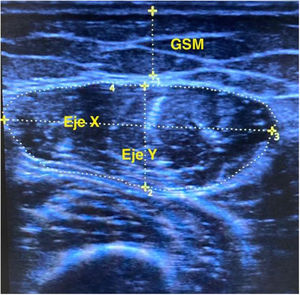

Muscle mass was measured by ultrasound using Digital Color Doppler Ultrasound equipment (SonoScape, China), following previously published protocols.20,21 The measurement was performed in B mode and with a linear probe (6−12 MHz), in the lower third of the imaginary line between the anterosuperior iliac spine and the patella of the dominant leg, in supine decubitus, with the muscle relaxed and with the transducer perpendicular to the longitudinal axis. We proceeded to measure the thickness of the rectus femoris muscle (RFM) X-axis/Y-axis, the area and supramuscular fat, as detailed in Fig. 1. To avoid errors in the measurements, we used the mean of 3 consecutive measurements from the same observer. These measurements were adjusted for height (Y axis /[height]2) and patient body surface area (Y-axis/BSA). For the calculation of body surface area we used the Du Bois and Du Bois formula.22

Ultrasound measurements of the rectus femoris muscle (RFM) are summarized in Table 1 and it is emphasized a significant reduction in thickness (Y) without changes in the horizontal axis (X), with a tendency to greater supramuscular fat. The parameters corrected for patient height and body surface area behaved in the same manner.

We propose the value of the RFM thickness (Y axis) as the most relevant parameter for monitoring the estimation of muscle mass. The loss of RFM mass estimated by area is significant, but the Y axis is more discriminating, since the sarcopenic muscle is more flaccid and, although it maintains the X axis, it loses thickness and increases supramuscular fat. The Y axis analyses are confirmed in the indices corrected by height or body surface of the patient, necessary for its standardization.